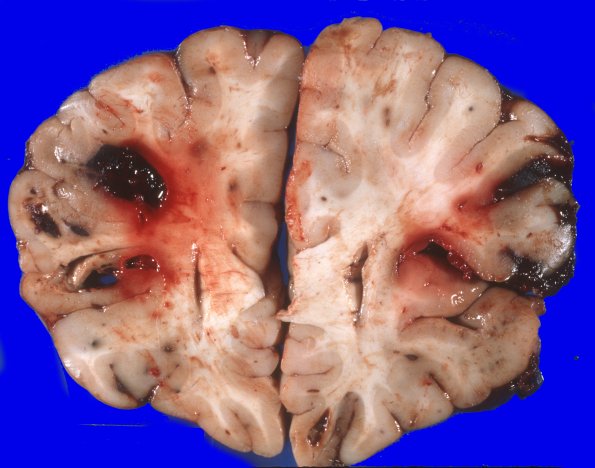

Washington University Experience | NEOPLASMS (HEMATOLYMPHOID) | Granulocytic Sarcoma | 4A2 Leukemic nodules (Case 4) gross 8

There is bilaterally symmetrical cerebral edema causing flattening of the gyri and narrowing of the sulci over both hemispheres. Cross sections of the bilateral cerebral hemispheres disclose multiple well circumscribed areas of hemorrhage, many at the cortical gray/white junction. These measure from approximately 1 mm to 2 cms in diameter. In some cases, the central portion of the hemorrhage appears to be made up of a pale appearing substance.